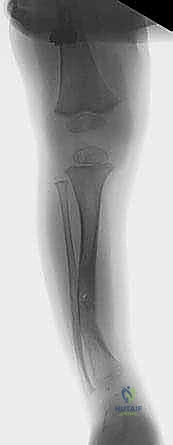

- عظمة الشظية (Fibula): تلعب الشظية (العظم الأصغر الموازي لقصبة الساق) دورًا ميكانيكياً مهماً. في العديد من الحالات، تكون الشظية منحنية أيضاً، أو مصابة بالالتحام الكاذب، أو حتى سليمة وأطول من قصبة الساق المكسورة. الشظية السليمة هنا تعمل كـ "دعامة مقاومة" تعيق محاولات الجراح لتصحيح استقامة قصبة الساق وضغط طرفي الكسر معاً. لذا، يتطلب الأمر غالباً إجراء قطع عظمي جراحي للشظية (Fibular Osteotomy) أو استئصال جزء منها.

الخطوة السادسة: التعامل مع عظمة الشظية

كما ذكرنا في التشريح، غالباً ما تعيق الشظية استقامة قصبة الساق. يتم إجراء شق منفصل لعمل قطع عظمي في الشظية (Fibular Osteotomy)، مما يسمح بتصحيح التشوه وتطابق نهايات قصبة الساق المكسورة بشكل مثالي.